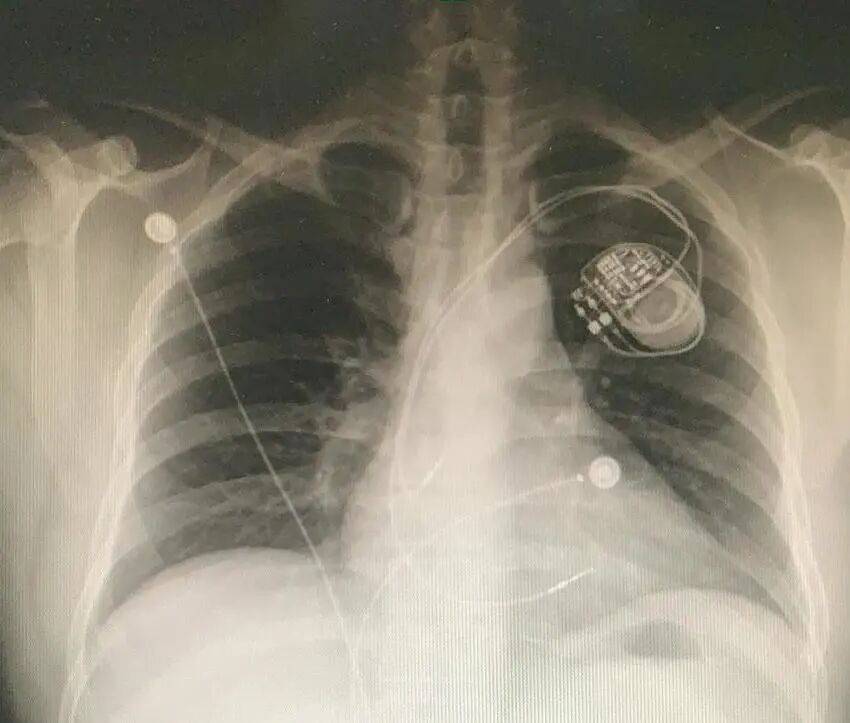

心脏起搏器、ICD

MRI检查:绝大多数不能做

在强磁场中,心脏起搏器、ICD可能会出现装置移位、起搏信号异常、除颤模式异常启动、电极升温等现象,严重时可导致装置损坏、心律失常甚至死亡等后果。

目前临床上应用的绝大多数心脏植入式电子设备都不能与MRI兼容。